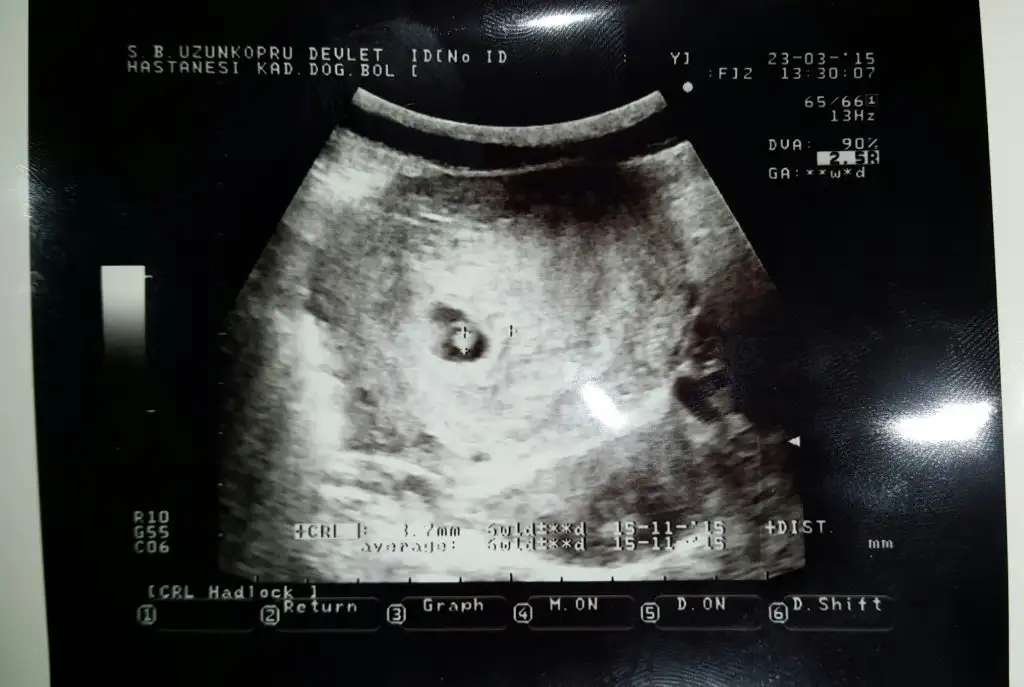

Sola yakın duruyo bence erkekKızlar 9haftalık benim de bakar mısınız biEki Görüntüle 1470198

Kese yus yuvarlak bence kız olacakKızlarr 7+4 sizce cinsiyeti ne olabilirEki Görüntüle 1472290 Eki Görüntüle 1472291

Vallacanım buna bakıncada içimden kız geçti ama gönlündeki ne bilmem kaçıncı bebek ilkse önemli deyil zaten6.hafta da uzundu simdi yuvarlak oldu :)))Eki Görüntüle 1472301